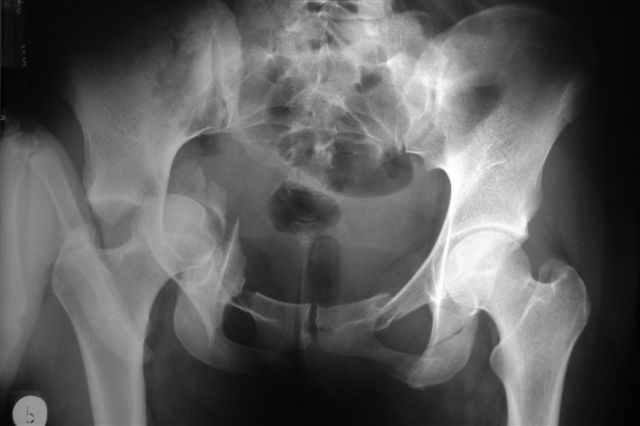

P.S. в приложении R пациентки с похожей проблемой доступа.. за исключением того, что перелом

двухколонный. Вертлугу лечили Y доступом.

К сожалению, далеко не все виды поперечно-ориентированных переломов хорошо лечить задним доступом (неважно на боку или на животе или в среднем положении, что я тоже делал в начале пути). Как только появляются необходимость управления передней колонной (Т-образный перелом, высокий двухколонный, импрессия) возникает выбор - или два доступа или один расширенный, чаще расширенный доступ на боку (Y), удобнее и не так страшно, если перелом оказался вдруг... .

Я предпочитаю в таких случаях расшириться Y-образно, и тогда этих проблем просто нет, тем более, что в этом случае головка извлекается мягко, не царапается хрящ, и репозиция лонноседалищного фрагмента идет сначала через перелом (банальным крючком) и лишь затем из седалищной вырезки (так спокойнее за седалищный нерв).